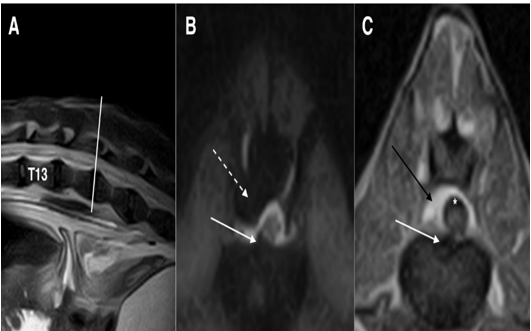

Diagnostic techniques: Blood exams were unremarkable. The dog was anesthetized with medetomidine (sedastart 1 mg/mL, all these are without compression of the spinal cord or sub-arachnoidal space highlighted using a contrast medium. Esteve) at a dose of 3 mcgr/Kg, administered with propofol (proposure 10 mg/mL, Merial) at a dose of 4 mg/Kg and maintained with isoflurane (2.5 %)/vetflurane (1000 mg/g, Virbac). The field of view of the first magnetic resonance imaging (MRI) scanners can was very small (14 cm). As our patient was large, we first performed a CT myelography (Toshiba Asteion dual slice) of the thoracolumbar spine, by intrathecal inoculation at the A after cerebrospinal fluid (CSF) tapping. The slice thickness was set to 3 mm using hard and soft tissue filters. The examination was T1 weighted imaging SET1WI (TE 26, TR 800 ms, Nex 3) on sagittal and transverse planes. The CT myelography can 1) and spin-echo completed using MRI (0.2T unit) (Esaote Vet Mr), with turbo spin-echo T2 weighted imagingTSET2WI (TE 80, TR 2600 ms, Nex revealed spondylosis of the vertebrae from T4 to T7, with multiple disc protrusions on the first lumbartract (Figure 1A-C).

Figure 1: multi-planar reconstruction (MPR) of CT myelography scan on sagittal (A), transverse (B), and dorsal (C) planes. White arrows indicate from T4 up to T7 (A) and at the level of T5-T6 (B) ventral spondylosis. Asterisk shows the disc protrusion in T5-T6 (B) while dashed black arrows (A) indicate multiple disc protrusions in T7-T8 and T8-T9.

This was confirmed as generalized disc degeneration using MRI (Figure 2), at sites T3-T4, T5-T6, T7-T8, T8-T9, T13-L1, and L1-L2, without compressions or signal changes of the spinal cord (Figure 1C, 3B, 4B-C and 5). Widening of the epidural and subarachnoid space was noted (Figure 4 B-C); this alteration was considered secondary to reduced transverse diameter of the spinal cord. CSF was normal on examination. After 23 months, a new MRI was performed using a 0.3T unit (Hitachi Airis II), with turbo spin-echo T2 weighted imaging (TSET2WI= TE 120, TR 5000, and Nex 4), spin-echo T1 weighted imaging (SET1WI= TE30, TR448, Nex 2), and short tau inversion recovery (STIR= TE 25, TI 110, TR 6000, and Nex 2) in the sagittal and transverse planes, confirming the previous findings.